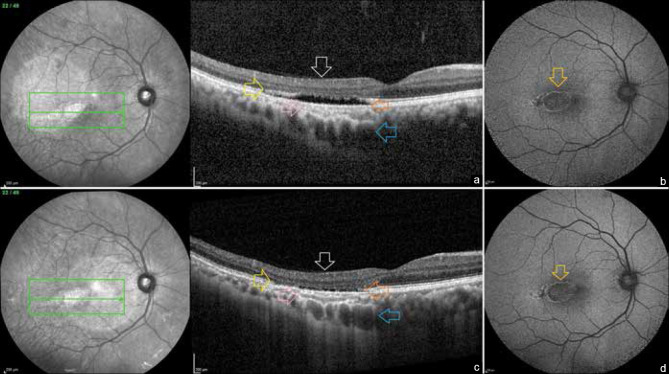

Results: A 37-year-old male, without any ocular symptoms, on dilated fundus examination showed a characteristic torpedo-shaped, flat, horizontally oriented, ovoid-shaped, hypopigmented chorioretinal lesion, temporal to the foveal center. At the most recent visit, after 6 years, the lesion exhibited changes on OCT, including the collapse of the subretinal cleft, the thinning of the retinal pigment epithelium (RPE) layer and inner choroidal layers, and the increased visibility of the underlying choroid and inner retinal excavation. The fundus autofluorescence demonstrated an increase in hypoautofluorescence in the center of the torpedo lesion, which was surrounded by a hyperautofluorescent boundary.

Conclusion: This appears to be the first report of longitudinal changes in a classic case of TM, demonstrating changes in the RPE, inner choroidal, and outer retinal layers over time.